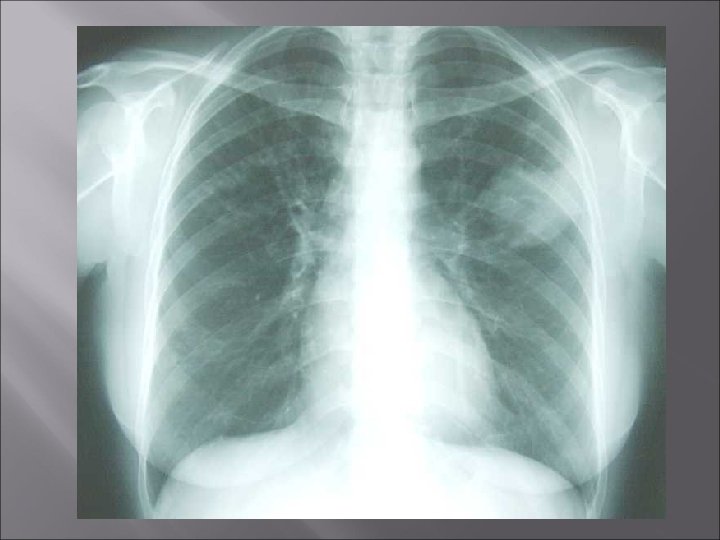

Imágenes Radiológicas v Nódulos y masas cavitadas o no v Vidrio esmerilado v Derrames pleurales v Las adenopatías hablan a favor de infección

Criterios diagnósticos: Wegener � T R Í � � A D � A � Inflamación de nariz o boca (ulceraciones, hemorragias, secreción purulenta) Infiltrados pulmonares en la Rx. Tx Sedimento nefrítico (>5 GR/campo, cilindros hemáticos) Histología: inflamación granulomatosa de la pared vascular y perivascular Al menos 2 de 4 criterios positivos: Sensibilidad 88%, especificidad: 92%

Enfermedad de Wegener: Rx Nódulos y masas pulmonares en el 90 % � Son granulomas que confluyen y se cavitan � Van de mm a 10 cm, múltiples, bilaterales � No hay predilección x área � 15 % imagen en halo vidrio esmerilado perinodular 50% responden al tto Respuesta al tratamiento 40 % de tamaño 10 % sin cambios �

Vasculitis Conclusions � The diagnosis of vasculitis is often delayed because a number of other disorders can mimic the clinical manifestations. Chest radiographs and especially CT are valuable for noninvasive diagnosis in patients with pulmonary vasculitis; � Certain radiologic signs in combination with clinical features enable an earlier diagnosis.